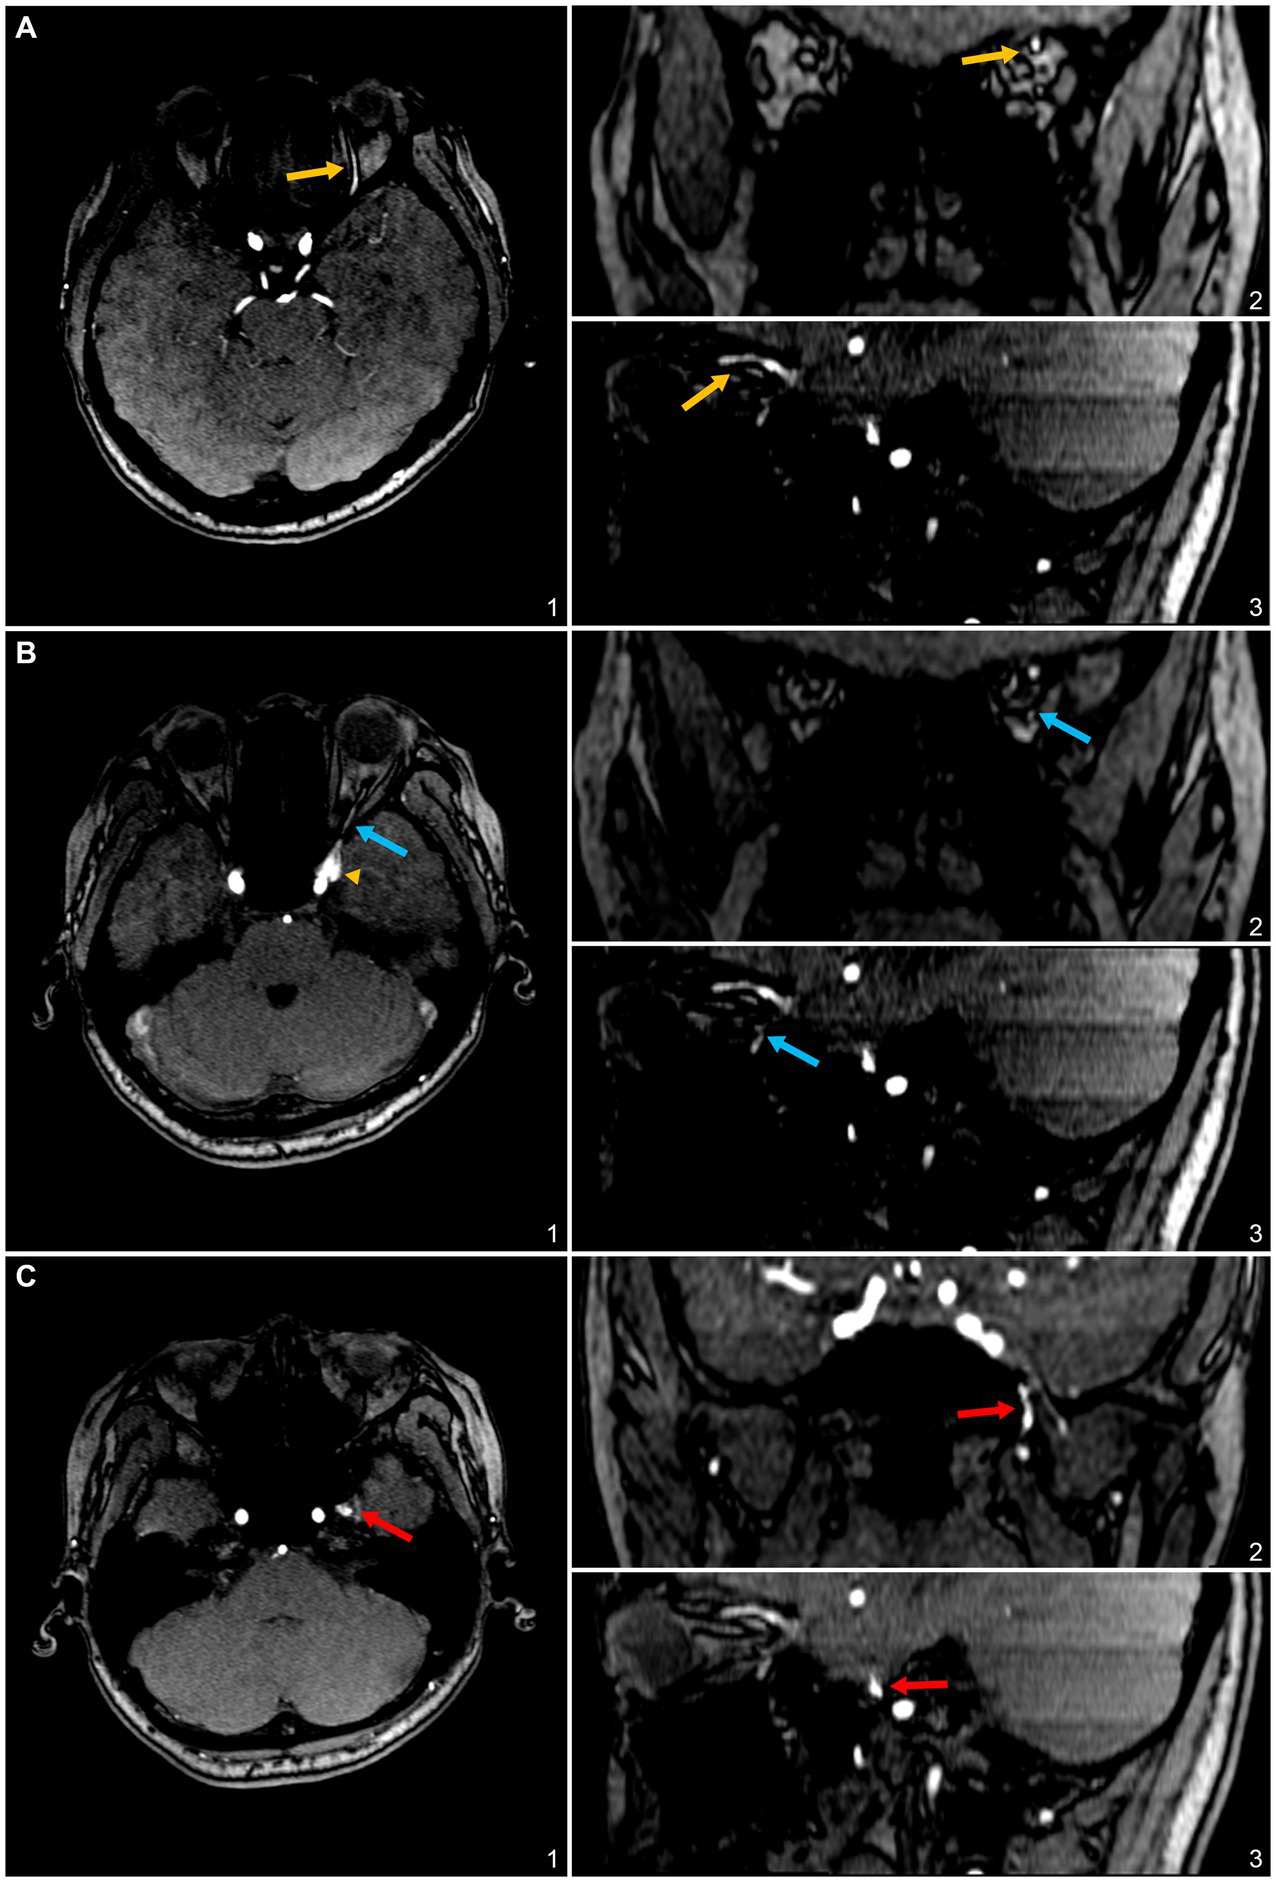

The patient had undergone both computed tomography (CT) and magnetic resonance (MR) scans. CT showed no signs of temporal bone dehiscence at either the sigmoid plate or the jugular bulb regions. The three-dimensional time-of-flight (TOF) MR angiography showed a relatively small region of hyperintense signal at the lesser SW region and the left para-CS (laterocavernous sinus) region (Figure 1), which extends to its efferent outlets, typically the SOV and inferior ophthalmic vein (IOV), and through the meningeal emissary veins to the pterygoid plexus (Figure 2). Upon this discovery, the subject was referred to interventional radiology/neurology. However, due to the patient’s unwillingness to undergo surgical intervention or digital subtraction angiography (DSA) examination, the subject chose conservative observation and took no medication, but was kept under follow-up care.

Figure 2

3D time-of-flight (TOF) magnetic resonance (MR) angiography slices highlighting the involved efferent venous pathways of the sphenoid wing (SW)-DAVF in this case. (A) Axial (1), coronal (2), and sagittal (3) slices depict the superior ophthalmic vein (SOV) as an efferent pathway, denoted by yellow arrows. (B) Axial (1), coronal (2), and sagittal (3) slices illustrate the inferior ophthalmic vein as a potential efferent pathway, indicated by blue arrows. (C) Axial (1), coronal (2), and sagittal (3) slices display the pterygoid plexus, marked with red arrows.